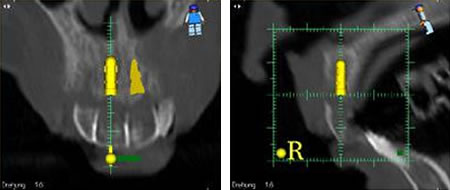

Im Vorfeld einer Implantation werden sehr genaue Informationen bezüglich des Knochenangebotes, der Knochenstruktur, der Wurzeln von Nachbarzähnen oder wichtiger anatomischer Strukturen wie Nerven oder die Kieferhöhlen benötigt. Die exakte Positionierung des Implantates unter Einbeziehung genannter Informationen ist für den Langzeiterfolg des Implantates entscheidend.

In schwierigeren Fällen, wenn zum Beispiel nur unzureichend Knochen vorhanden ist, die Lage der Nachbarzähne ungünstig erscheint oder evt. Nerven gefährdet sein könnten, werden im Vorfeld computertomographische Schichtröntgenaufnahmen benötigt. Während der Aufnahmen trägt der Patient bereits eine Schablone im Mund, welche die späteren "neuen Zähne" darstellt. Diese finden sich auf den Röntgenbildern wieder.

Die Röntgendaten werden in den Computer eingelesen. Es entsteht ein 3-dimensionales Abbild der Zahn-Kieferverhältnisse. Anhand dieses Bildes kann die exakte Position in Winkel und Tiefe der zu setzenden Implantate bestimmt werden. Die gewonnenen Positionierungsdaten können 1:1 auf die Schablone übertragen werden. In der Schablone werden entsprechend der Planung Bohrhülsen eingearbeitet, die eine genaue gewebeschonende Platzierung des Implantates, im richtigen Winkel und der richtigen Tiefe sicherstellen. Die Gefahr von Verletzungen der Nachbarzähne, Nerven oder sonstigen wichtigen anatomischen Strukturen, kann somit nahezu ausgeschlossen werden.